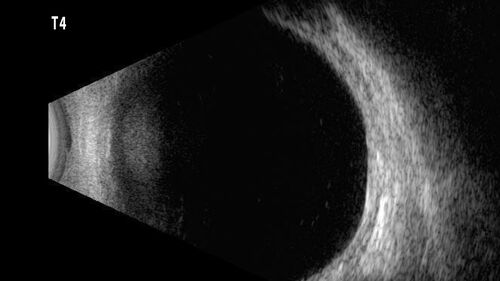

32 year old female with normal vision and CHRPE

CHRPE - with FA